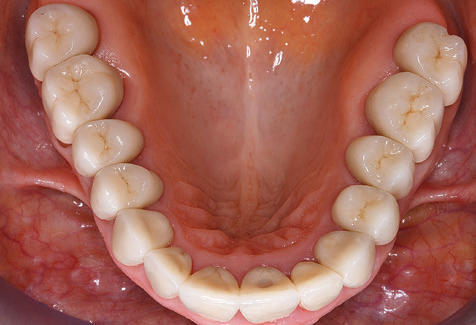

A 52-year-old patient presented in our clinic for the first time in 2004 following tooth loss in the third quadrant, expressing a desire for a new prosthetic restoration. Periodontal and radiological diagnostics revealed the need for extensive periodontological treatment. In addition, teeth 48, 28 and 27 were attributed a very poor prognosis and were subsequently extracted (Fig. 1). Following the successfully completed, systematic periodontological treatment, a fixed dental implant was inserted with the introduction of five implants in tooth regions 35, 36, 37, 46 and 47. Prosthetic treatment of the natural teeth was effected with veneered zirconium dioxide ceramic crowns; the implants were composed of two-piece, individual zirconium dioxide abutments and similarly veneered crowns made of a zirconium dioxide ceramic (Cercon base colored, Dentsply Sirona Lab). Definitive insertion of the prosthetic restoration occurred in 2005.

Due to the presence of periodontal disease, SPT was performed every three months in the first years following the insertion. The patient demonstrated a high degree of motivation and good compliance. The pocket depths recorded annually revealed a stable periodontal situation with a BOP index of below five per cent. On the basis of the stable periodontal situation and good cooperation on the patient’s part, the recall interval was extended to every six months as of the sixth year of the prosthetic function phase. Following the change in the recall interval, the respective annual documentation of the periodontal status continued to reveal a stable periodontal situation with no increase in the pocket depths and a BOP index below five per cent (Fig. 2a and b).

Standardised and regular risk-adapted care in the scope of SPT is the key to treatment success for the clinical long-term success in periodontically compromised patients. This is particularly true for patients fitted with implants following successfully completed periodontal treatment (Fig. 11a and b).